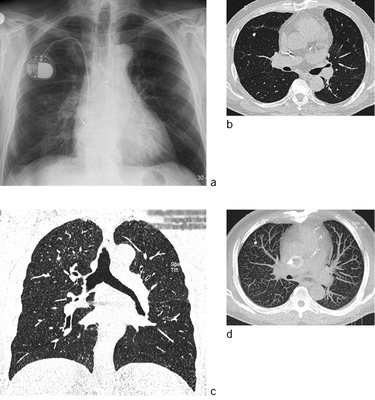

Nachdem durch arbeitshygienische Maßnahmen die komplizierten verschwielenden Verlaufsformen der Silikose nahezu völlig zurückgedrängt wurden, steht heute die chronische obstruktive Emphysembronchitis mit ihren schweren Folgen für die kardiorespiratorische Funktion im Vordergrund. Bereits 1972 wurde durch Otto u. von Hinüber beschrieben, dass die verschiedenen Formen des Emphysems unabhängig von lokalen Staubablagerungen und silikotischen Knötchen bei Autopsien beruflich staubbelasteter Personen deutlich häufiger als bei Autopsien nicht staubbelasteter Personen auftreten. Es finden sich fokale und generalisierte Emphysemformen wie das perinodöse Traktionsemphysem, das dilatative zentrilobuläre Emphysem bis hin zur generalisierten Form der sog. „schwarzen Löcherlunge“ sowie das bullöse bronchostenotische Emphysem, häufig mit einer persistierenden Bronchitis und Bronchiolitis kombiniert. Bei ausgeprägtem Lungenemphysem können anhand der Übersichtsaufnahme silikotische Noduli vollständig entgehen. Computertomographisch zeigen sich in diesen Fällen häufig neben dem ausgeprägten Emphysem zusätzlich Bronchialwandverdickungen als Zeichen einer Bronchitis sowie unscharfen zentrilobulären Knötchen als Zeichen einer Bronchiolitis und scharf berandete Noduli im Sinne silikotischer Knötchen (  Abb. 7 ). Das Ausmaß des Lungenemphysems korreliert nach Literaturangaben wohl deutlich mit der Einschränkung der Lungenfunktion, eine gute Korrelation mit der Ausprägung der nodulären Veränderungen besteht jedoch nicht (Bergin et al. 1986; Gevenois et al. 1998; Lopes et al. 2008; Meijer et al. 2011).